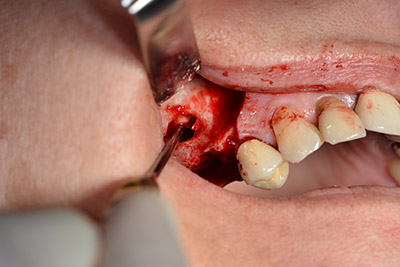

Хирургична процедура за имплантиране

Класическият разрез (крестално, букално освобождаване) и подготовката на мукопериостално ламбо осигуряват добра видимост.

Следващата стъпка е синус лифт с непосредствено имплантиране. Implantmed е предварително настроен на първа позиция за букална фенестрация на стената на максиларния синус.

Фенестрацията е извършена при 35,000 rpm и след това носната лигавица е обработена по посока на челюстта (Фиг. 13 to 14).